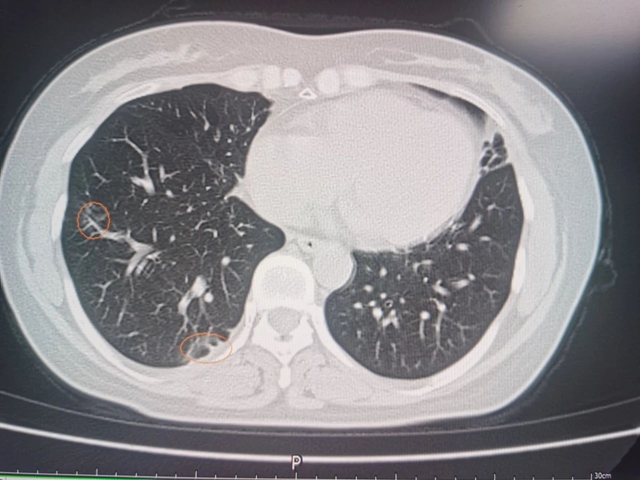

一年后复查,肝右前叶近肝缘小结节灶、肝右叶病灶内壁结节较前明显减小;但甲胎蛋白较前升高,通过胸部CT检查发现肺部两个实性结节,综合患者病情考虑肿瘤复发伴肺部转移,又为其实施了“CT引导下肝肿瘤肺转移灶微创消融术”,术后定期复查患者肝功能、甲胎蛋白均未见异常,病情稳定。

术后胸部CT